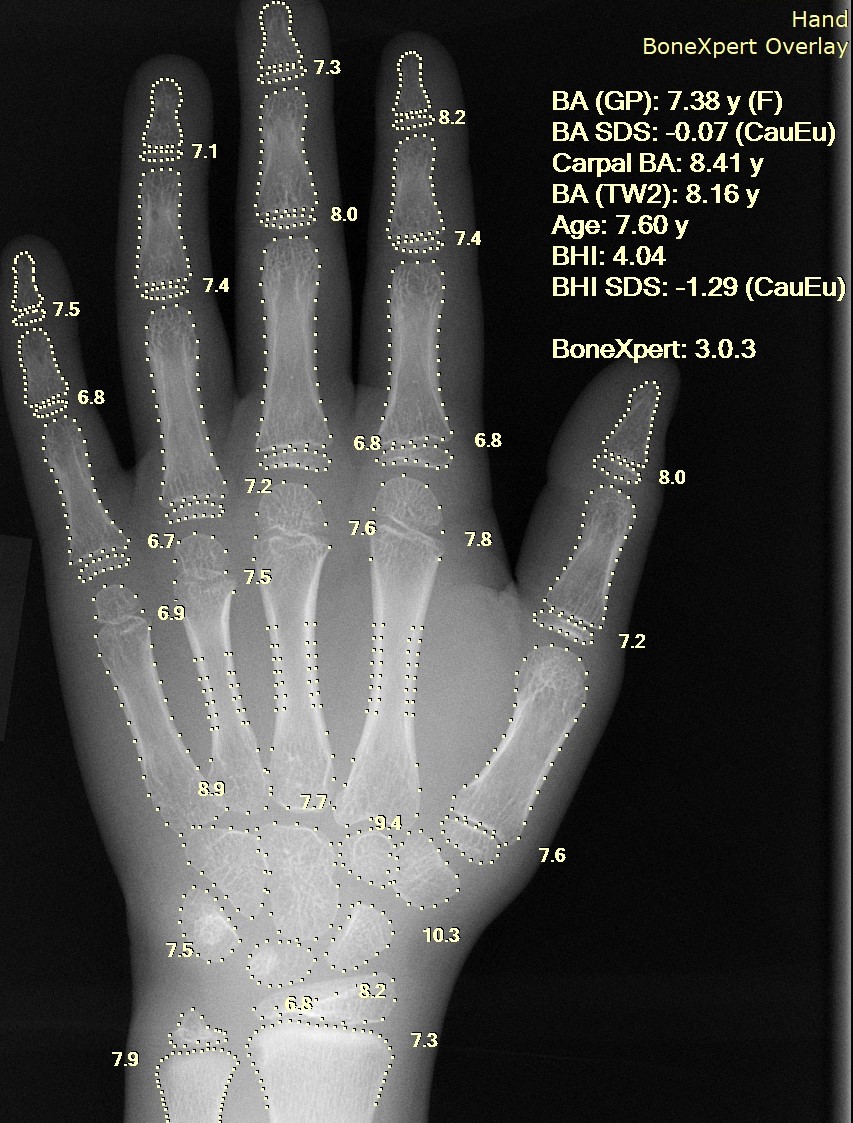

4. 2. 영상 검사

뼈의 성숙도는 전반적인 신체 성숙을 보여주는 좋은 지표이다. 따라서 뼈 나이를 평가하기 위해 왼쪽 손과 손목의 X-ray 촬영을 시행한다. 이를 통해 해당 아이가 사춘기가 시작되어야 하는 신체적 성숙 단계에 도달했는지 확인할 수 있다.[1][9][91][83] X-ray 검사 결과, 실제 나이와 관계없이 골연령이 여자아이의 경우 11세 미만, 남자아이의 경우 13세 미만이라면 대부분 체질적인 사춘기 지연으로 판단한다.[9][35][83][120]